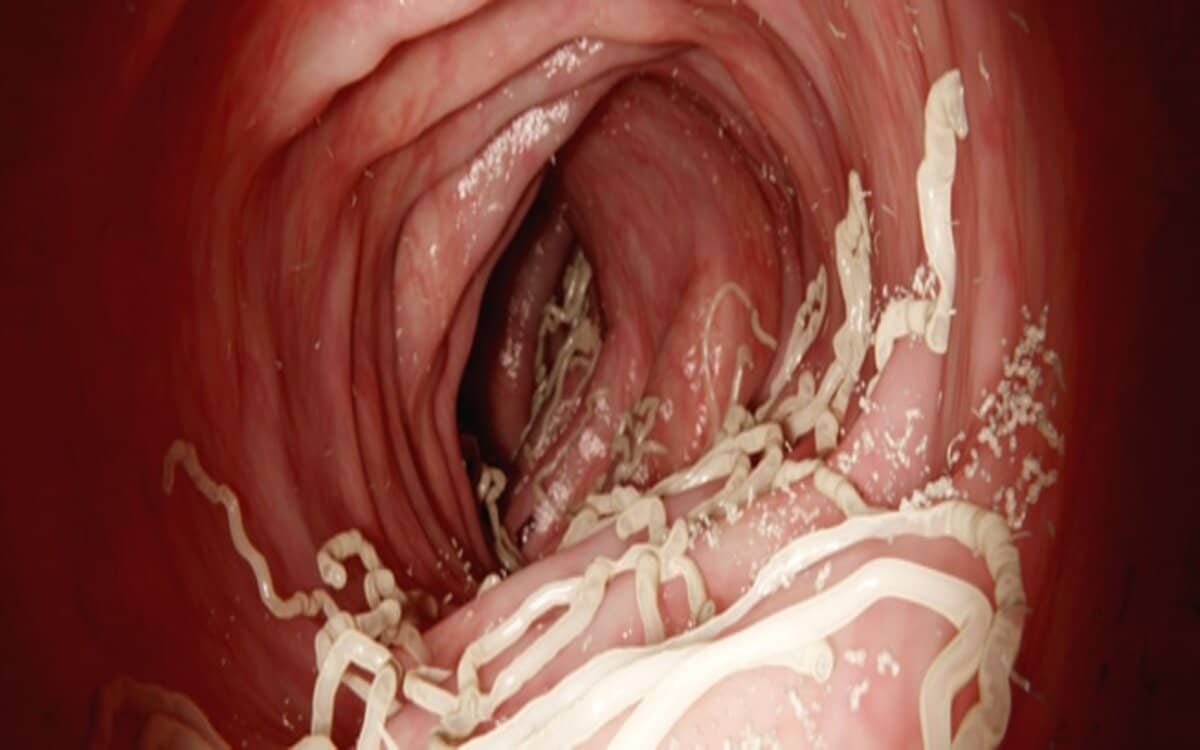

وتظهر ديدان المؤخرة حول منطقة فتحة الشرج وأحيانًا حول المهبل لدى السيدات والفتيات الصغار، وذلك نتيجة الإصابة بعدوى طفيلية في الأمعاء، وهذا المقال سنتعرف على كيفية التخلص من ديدان المؤخرة بعدة طرق نستعرضها خلال السطور التالية.

- ملاحظة ديدان صغيرة في البراز.